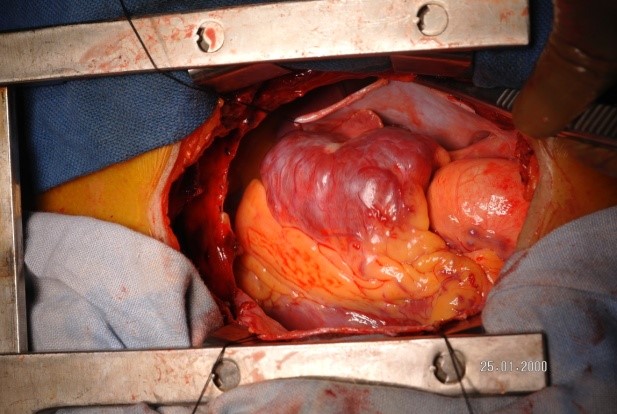

The patient was taken to surgery for a right atrial myxoma excision. A median sternotomy and pericardiotomy was done. Surprisingly, upon examination an 8 x 5 cm mass was found outside the right atrium (RA), adherent to part of the RA wall and encircling the RCA. The patient was placed on cardiopulmonary bypass with cardioplegic arrest. The mass was carefully dissected and removed en-bloc along with part of the RCA. The ostium of the RCA was sutured and buried. Pericardium was harvested and used to reconstruct the RA wall. The tricuspid valve was examined and checked for valve regurgitation. A saphenous vein graft was harvested from the left leg. The distal anastomosis to the RCA and the proximal anastomosis to the aorta were done with 7-0 and 6-0 prolene sutures, respectively. Distal flow was confirmed with a Doppler probe. The patient was gradually weaned off of cardiopulmonary bypass and the chest was closed in layers.

The excised mass was sent for histopathological examination where a gross cut section showed a yellowish to greyish-brown mass. Microscopic examination revealed nests of oval to elongated cells with eosinophilic cytoplasm, oval to elongated nuclei, and fine chromatin, morphology that is consistent with paraganglioma. An immunohistochemistry panel showed tumor cells positive for chromogranin A and synaptophysin, confirming the paraganglioma diagnosis.